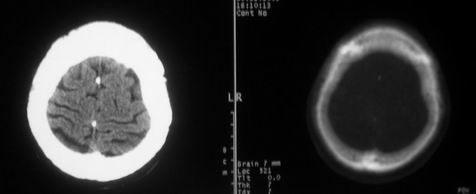

女,72岁,头晕。额骨有无问题。

额骨呈磨玻璃状增厚,考虑骨纤。

额骨呈磨玻璃状增厚,考虑骨纤

考虑额骨良性骨板肥厚;骨纤待排。

左额部骨瘤